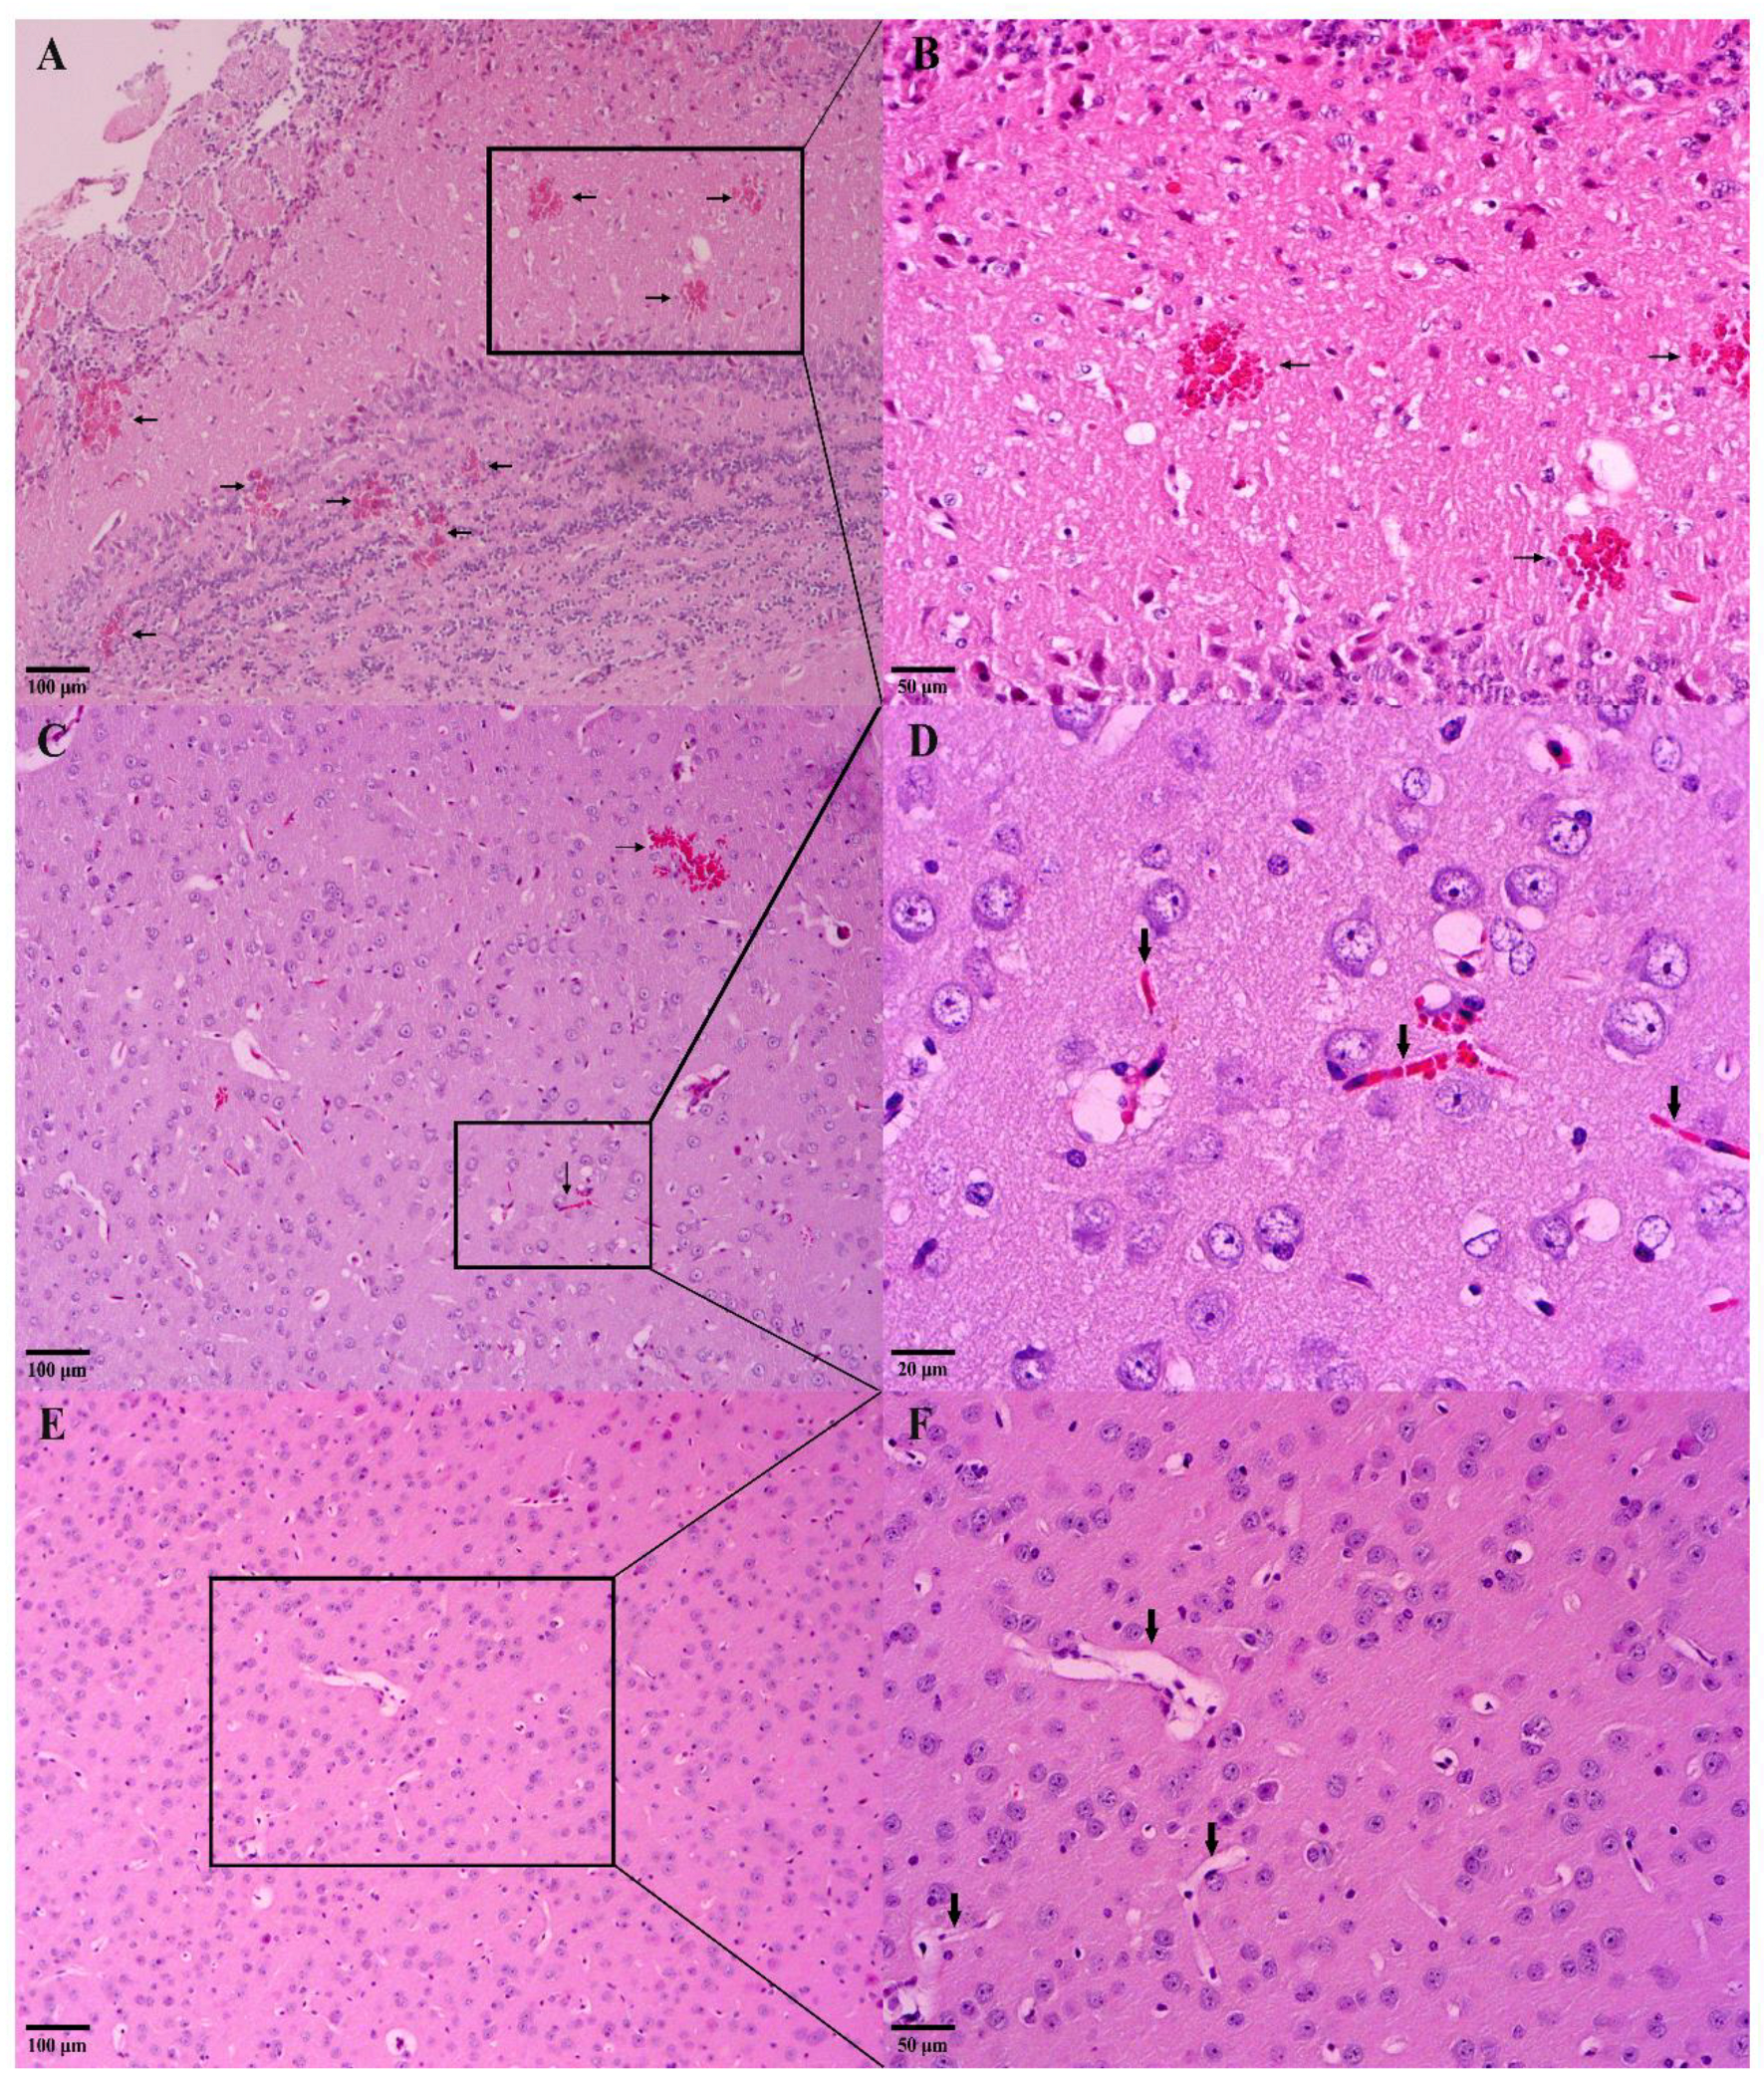

2.5.5. Macroscopic and Histological Analysis of the Brain